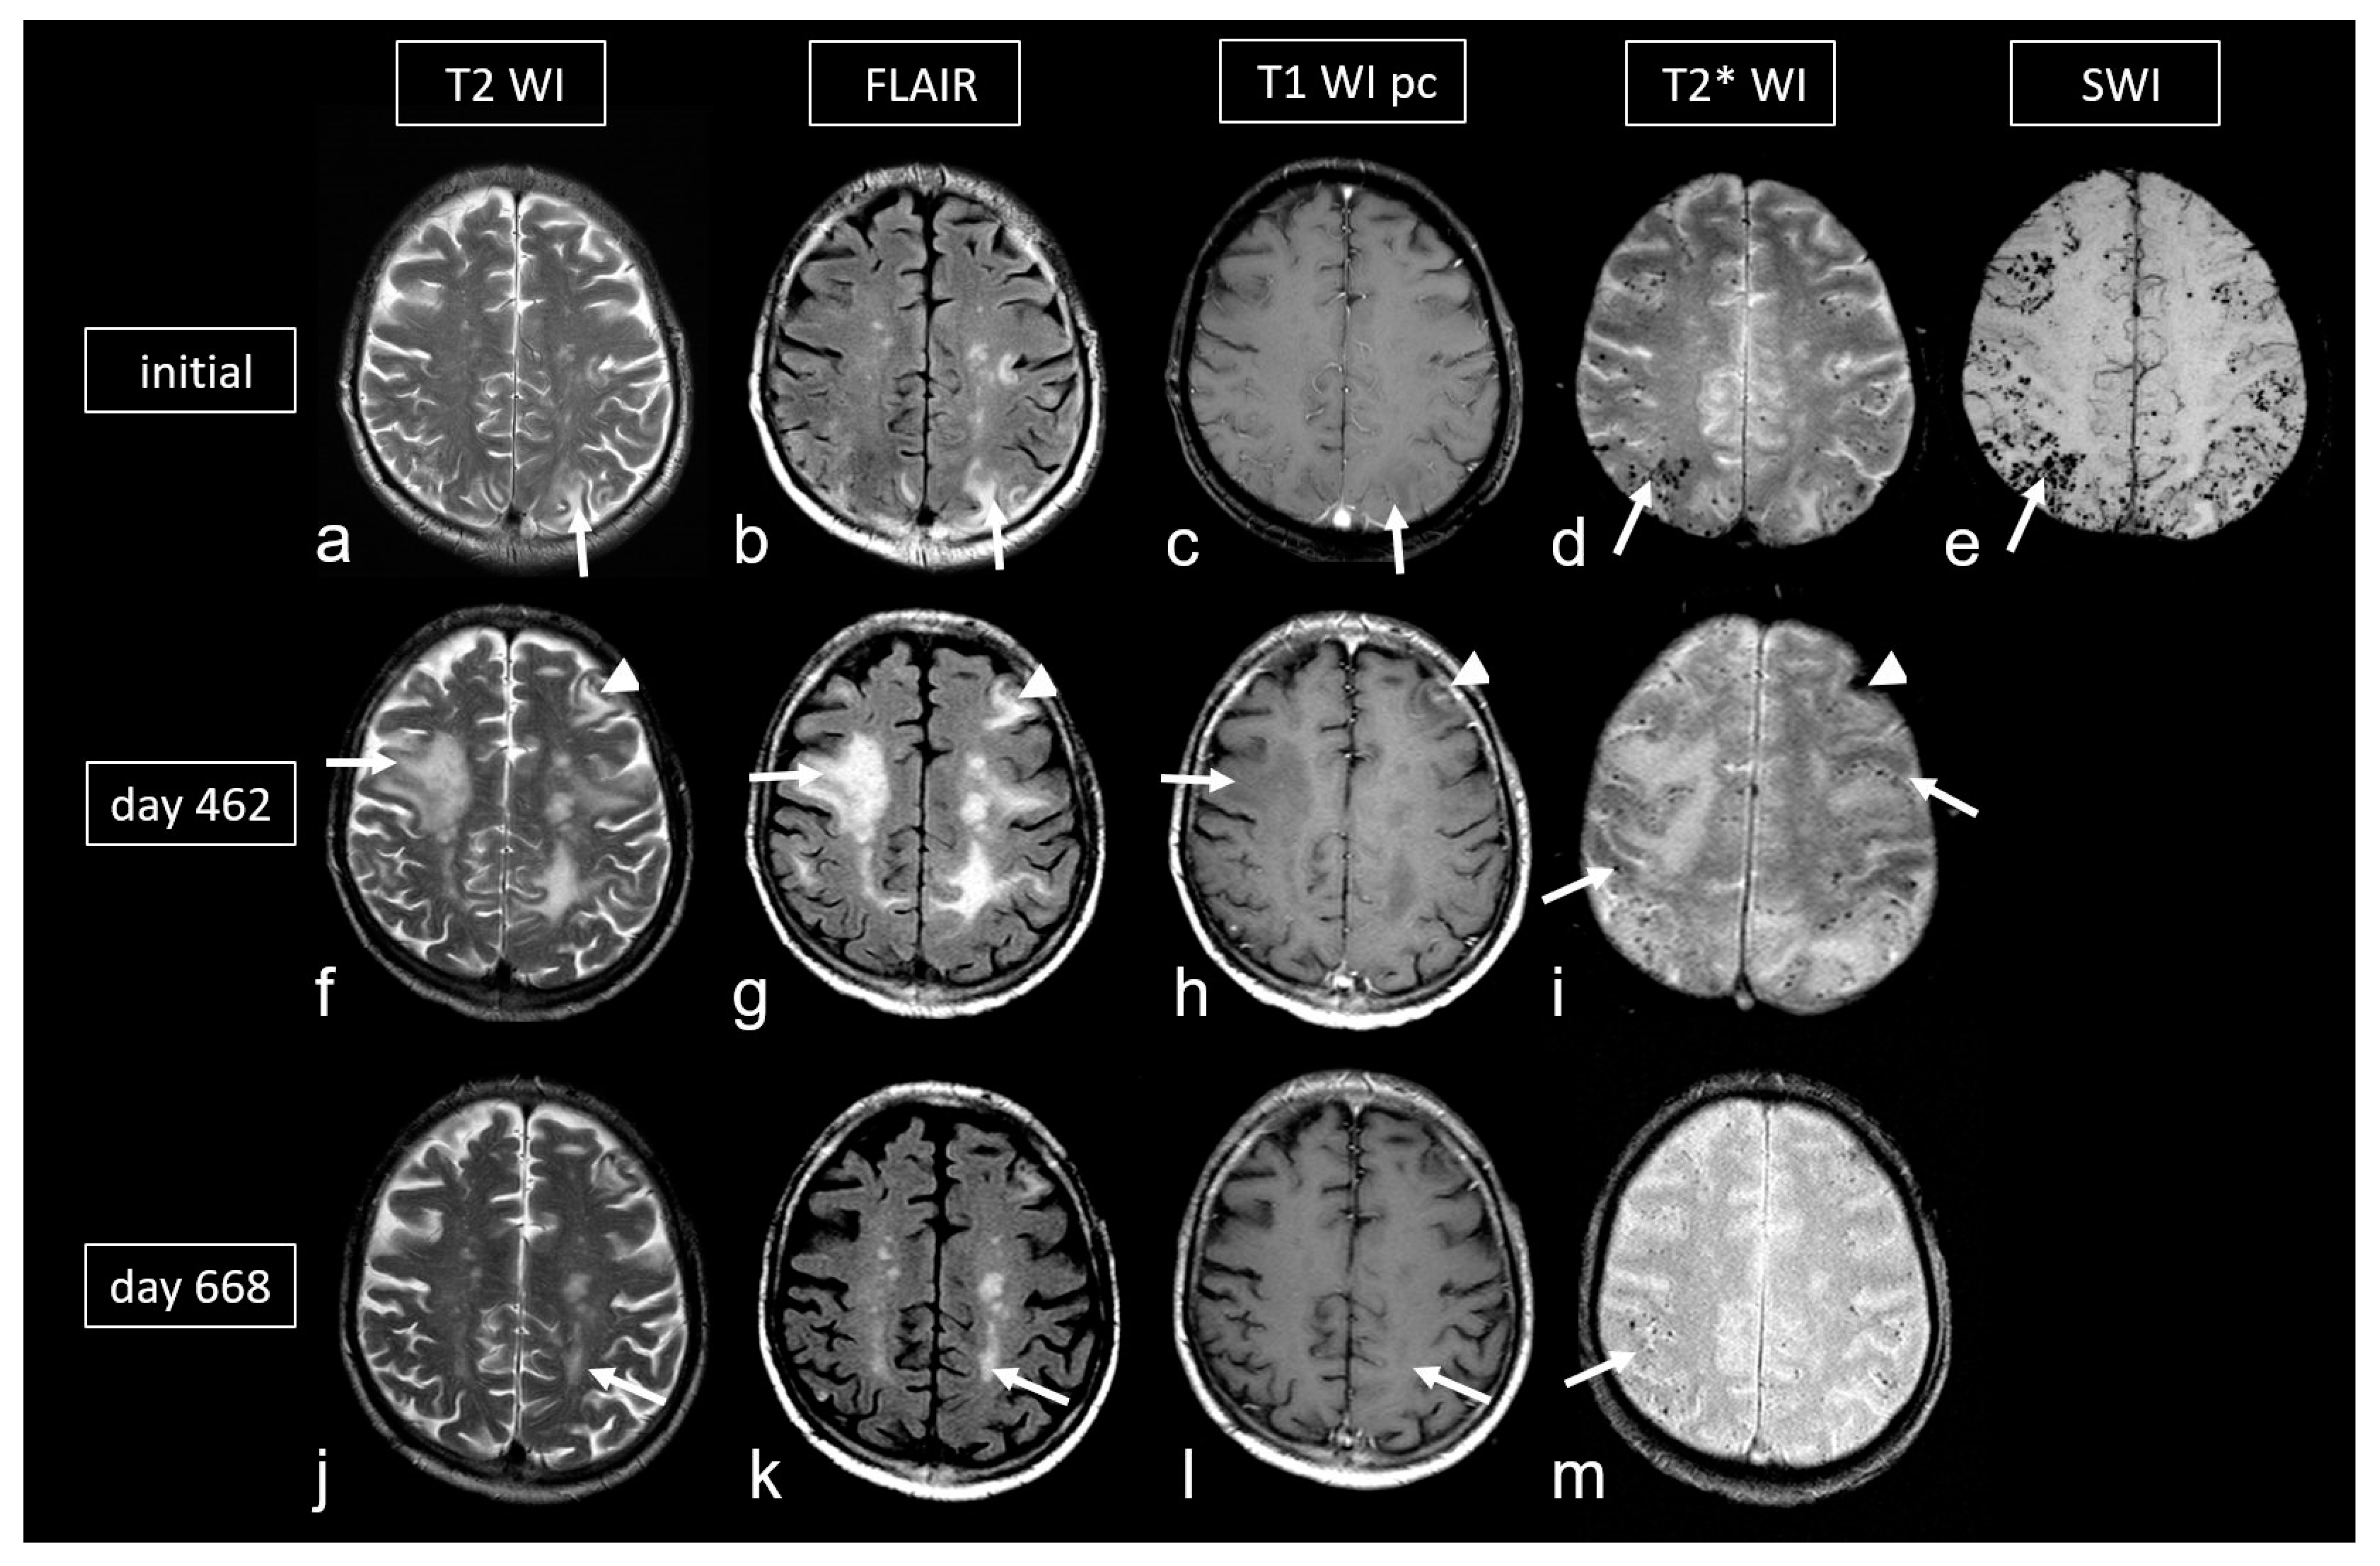

Figure 6.

Cerebral amyloid angiopathy-related inflammation (CAA- ri) in a 72-year-old man suffering from subacute deterioration of consciousness and dizziness. (a–e): Initial MRI (upper row; MRI 3.0 T Siemens Magnetom) showing several hyperintense lesions preferentially in the subcortical occipital region ((a,b): arrow) without contrast enhancement on post-contrast T1-weighted images (T1 WI pc; (c), arrow), focal-accentuated microbleeds (MB) on T2* WI ((d), arrow) and susceptibility-weighted imaging (SWI; (e), arrow); note the higher sensitivity for MB on SWI (e) compared to T2* WI (d). (f–i): MRI (1.5 T Intera, Philips Healthcare) at readmission due to subacute severe psychosyndrome after tapered corticosteroid therapy. Multiple occasionally space-occupying hyperintense white matter lesions ((f,g): arrow) without contrast enhancement ((h), arrow) and progressive bilateral MBs ((i), arrow). Note the additional subacute small left frontal intracerebral hemorrhage (ICH; arrowhead). (j–m): Follow-up MRI (1.5 T Intera, Philips Healthcare) after several bouts of intravenous high-dosage methylprednisolone showing distinct regression of white matter lesions ((j,k): arrow) without contrast enhancement ((l), arrow), no significant new hemorrhagic lesions (m).

CAA-related inflammation (CAA-ri) is a subtype of CAA characterized by the presence of autoantibodies against Aß in the arterial vessel walls [95,96,97,98,99,100]. The inflammation, which affects both the vascular and perivascular regions, leads to vasogenic edema and leptomeningeal effusions, resulting in hyperintense signal changes on T2-weighted sequences [96,100]. These MRI features are identical to the imaging changes observed during amyloid antibody therapy [97,101,102], in which these are known as “amyloid related imaging abnormalities” (ARIA) (Figure 6) [101,102,103,104,105]. ARIA-E (edema, effusion), characterized by circumscribed peripheral edema often involving the cortex [101,106,107], is frequently accompanied by MBs, cSAH or cSS (ARIA-H, hemorrhagic) resulting in overall picture that aligns with CAA-ri, making both entities morphologically indistinguishable [101,103,104,105].